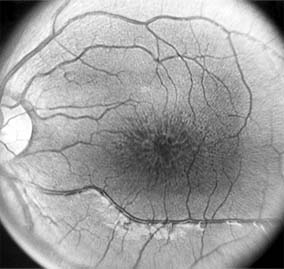

MACULAR EDEMA

Retinal edema involving the macula may be associated with a variety of intraocular inflammatory diseases, retinal vascular diseases, intraocular surgery, inherited or acquired retinal degenerations, medications, macular membranes, or unknown causes. Macular edema may be diffuse, with nonlocalized intraretinal fluid causing thickening of the macula. When edema fluid accumulates in honeycomb-like spaces of the outer plexiform and inner nuclear layers, it is called cystoid macular edema. On fluorescein angiography, fluorescein dye leaks from the perifoveal retinal capillaries and accumulates in a flower-petal pattern about the fovea (Figure 10-4).

Figure 10-4

Figure 10-4: Flower-petal pattern of fluorescein dye in a patient with cystoid macular edema after cataract surgery.